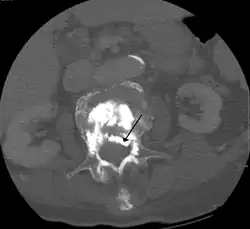

During the procedure, bone cement is injected with a biopsy needle into the collapsed or fractured vertebra. The needle is placed with fluoroscopic x-ray guidance. The cement (most commonly poly methyl methacrylate (PMMA), although more modern cements are used as well) quickly hardens and forms a support structure within the vertebra that provide stabilization and strength. The needle makes a small puncture in the patient's skin that is easily covered with a small bandage after the procedure.[2]

Some of the associated risks are from the leak of acrylic cement to outside of the vertebral body. Although severe complications are extremely rare, infection, bleeding, numbness, tingling, headache, and paralysis may ensue because of misplacement of the needle or cement. This particular risk is decreased by the use of X-ray or other radiological imaging to ensure proper placement of the cement.[2] In those who have fractures due to cancer, the risk of serious adverse events appears to be greater at 2%.[23]